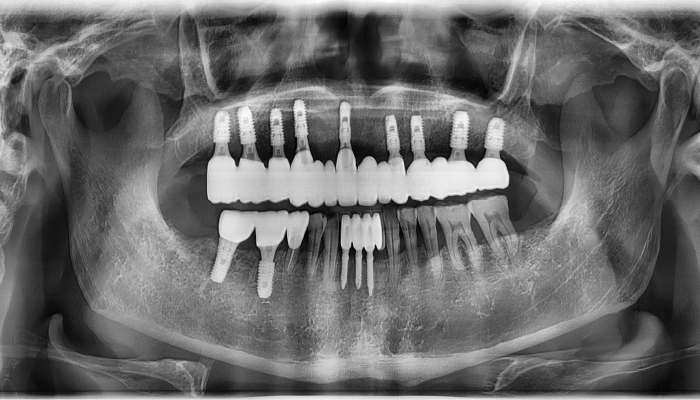

뼈이식 임플란트 전후 사례

• 식립 전

식립 후